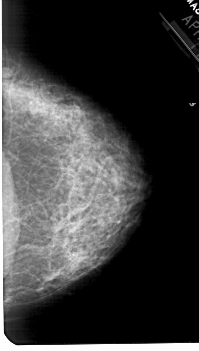

A_1777_1.RIGHT_CC

RIGHT_CC LINES 5251 PIXELS_PER_LINE 2971 BITS_PER_PIXEL 12 RESOLUTION 43.5 NON_OVERLAY